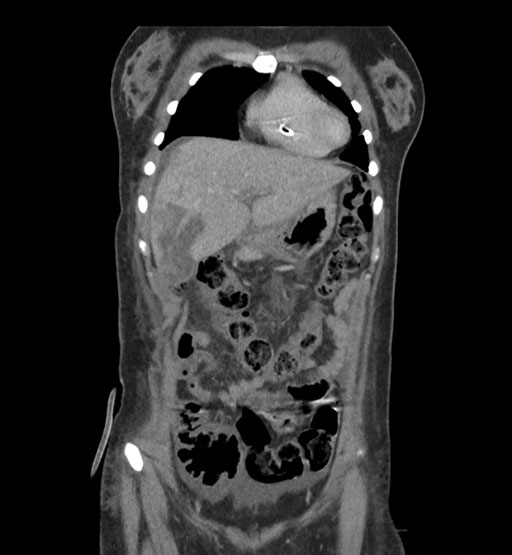

Coronal Venous